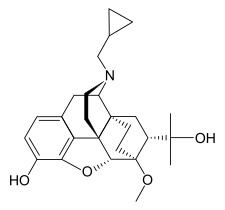

The pharmacodynamic response to an opioid depends upon the receptor to which it binds, its affinity for that receptor, and whether the opioid is an agonist or an antagonist. For example, the supraspinal analgesic properties of the opioid agonist morphine are mediated by activation of the μ1 receptor; respiratory depression and physical dependence by the μ2 receptor; and sedation and spinal analgesia by the κ receptor. Each group of opioid receptors elicits a distinct set of neurological responses, with the receptor subtypes (such as μ1 and μ2 for example) providing even more [measurably] specific responses. Unique to each opioid is its distinct binding affinity to the various classes of opioid receptors (e.g. the μ, κ, and δ opioid receptors are activated at different magnitudes according to the specific receptor binding affinities of the opioid). For example, the opiate alkaloid morphine exhibits high-affinity binding to the μ-opioid receptor, while ketazocine exhibits high affinity to ĸ receptors. It is this combinatorial mechanism that allows for such a wide class of opioids and molecular designs to exist, each with its own unique effect profile. Their individual molecular structure is also responsible for their different duration of action, whereby metabolic breakdown (such as N-dealkylation) is responsible for opioid metabolism.

Several semi-synthetic opioids were developed in Germany in the 1910s. The first, oxymorphone, was synthesized from thebaine, an opioid alkaloid in opium poppies, in 1914.[228] Next, Martin Freund and Edmund Speyer developed oxycodone, also from thebaine, at the University of Frankfurt in 1916.[229] In 1920, hydrocodone was prepared by Carl Mannich and Helene Löwenheim, deriving it from codeine. In 1924, hydromorphone was synthesized by adding hydrogen to morphine. Etorphine was synthesized in 1960, from the oripavine in opium poppy straw. Buprenorphine was discovered in 1972.[228]